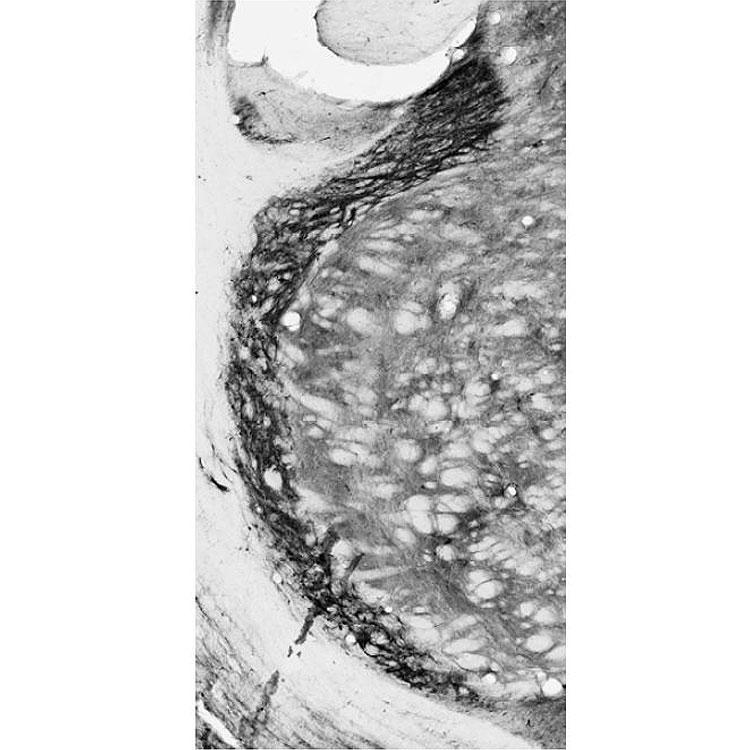

Supportive validation

- Submitted by

- Antibodies Incorporated / NeuroMab (provider)

- Main image

- Experimental details

- Adult rat hippocampus immunohistochemistry.

- Adult rat reticular thalamic nucleus immunohistochemistry.